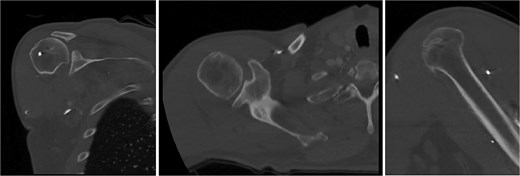

Both shoulders were reduced urgently by the orthopedic team, with immediate improvement in paresthesias (Fig. 2). Post-reduction CTs were significant for bilateral chronic rotator cuff disease with superior migration of the humeral heads, right-sided supraspinatus and subscapularis atrophy, and a left nondisplaced glenoid fracture (Figs 3 and 4). He was discharged home in bilateral slings.

Post-reduction CT of the right shoulder demonstrating superior humeral head migration relative to the glenoid, visualized evidence of prior rotator cuff repair surgery, and a nondisplaced anterior-inferior glenoid fracture.